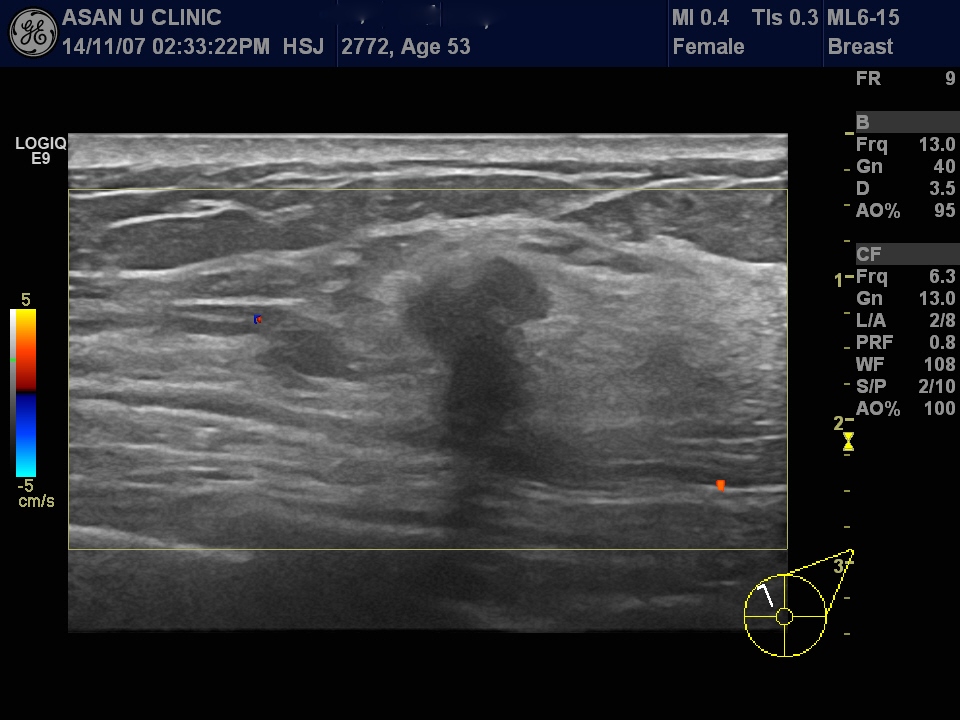

갑자기 만져지는 좌측 유방의 상내측 유방 멍울과 통증으로 내원한 53세 여성입니다.

본원 유방초음파상 만져지는1.4cm의 오똑한 저에코의 결절이 있었으며

조직검사 시행하여

침윤성 유방암 진단되었습니다.

다행이 액와림프절 전이는 의심되지 않습니다.